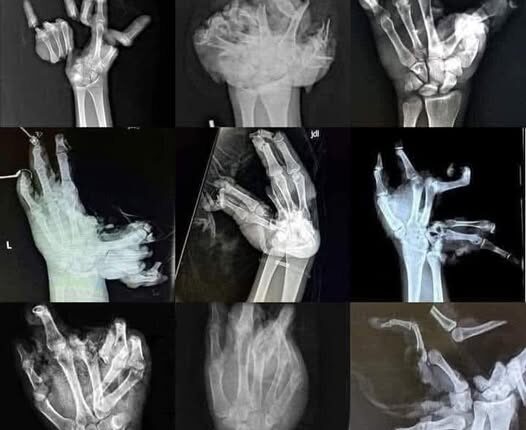

Доктор Александар Каревски, ортопедски хирург од Скопје, објави на својот профил на Фејсбук предупредување во врска со користењето на пиротехнички средства. Објави рентген снимка која е вистинска слика за опасностите од петардите

Своето предупредување го проследува со рентген снимки од шаки со страшни повреди од пиротехнички средства за кои напоменува дека им припаѓаат на оние посреќните, навестувајќи дека најчесто ова поминува со многу потешки последици.

Меѓу најчестите повреди предизвикани од ракувањето со петарди и пиротехнички средства се комплексни повреди на шаки со траен инвалидитет, изгореници на кожа, ампутации на прсти и раце, како и повреди на очите и лицето.